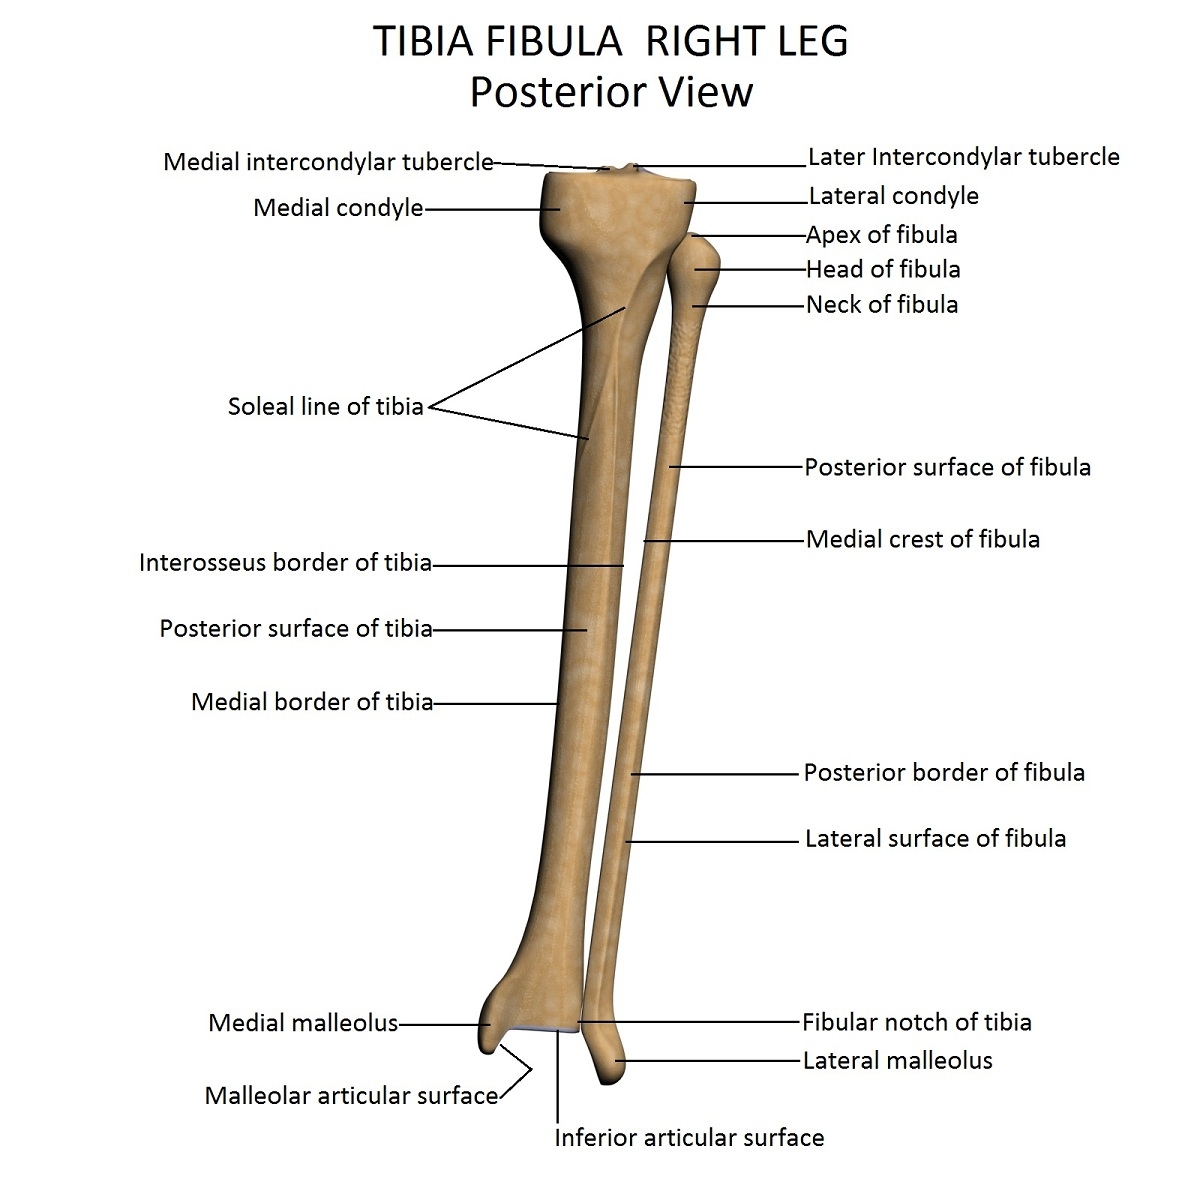

Tibia Fibula | Gross Anatomy | Anjani Mishra

Tibia and Fibula Osteology of the Leg and Knee

The Tibia – Proximal – Shaft – Distal – TeachMeAnatomy

The Fibula – Surfaces – Articulations – Fractures – TeachMeAnatomy